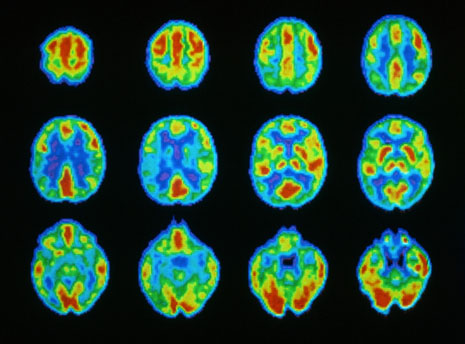

What I am not, could not, and would never choose to have been was some kind of clinical neuroscientist. As you might expect from my problem in lectures, I’ve never found the intricacies of neuroimaging, neuropharmacology or neurophysiology, to name but a few of the specialties with that prefix, very exciting. Perhaps it’s because those subjects were so poorly taught to me. I get lost very quickly when I listen to someone who is talking with enormous enthusiasm, for example, about the genetics of mental illness, because sooner or later they go into minutiae that seem so far away from the ‘person’ that my brain moves to its economy setting then switches off completely.

However one of the major problems I have with neuroscience is that despite the amount of money that has been poured into researching the brain there is still so little to show that is relevant to patients. I started training more than 35 years ago, and we have been repeatedly told that the day when this investment will result in real clinical improvement is somewhere just over the horizon.

Psychiatrists cannot simply become ‘clinical neuroscientists’ or even- as some have suggested, neurologists for several reasons. Clinical neuroscience is not yet ready for clinical use. There is still a great deal to do before that point will be reached and the brain is an infinitely complex organ. Furthermore we mustn’t forget that the person who inhabits that brain is very complex too, and lives in an increasingly complex world. I have spent my life trying to help others achieve change, facilitate health care systems to change, and grow and change in my self. None of these were straightforward and I often failed.